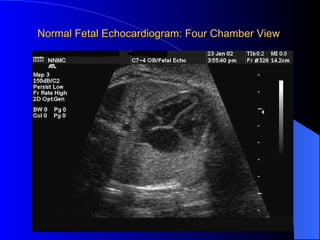

Normal Fetal Echocardiogram: Four Chamber View

Prenatal Assessment  Obstetric history Genetic evaluations Prenatal ultrasound  Fetal echocardiography 60% of cardiology admissions at CHOP prenatally diagnosed  49% of HLHS admissions at Children’s Hospital of Wisconsin were prenatally diagnosed